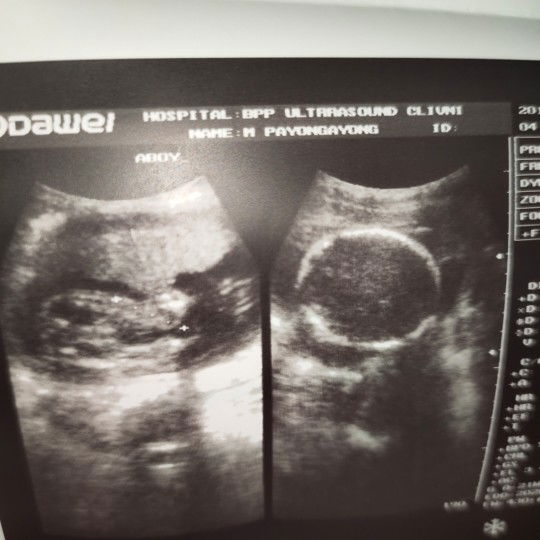

boy or girl

sav nung nag ultra its a baby boy ... im confused .. haha tingin ko kasi girl sya ... what do you think p0?